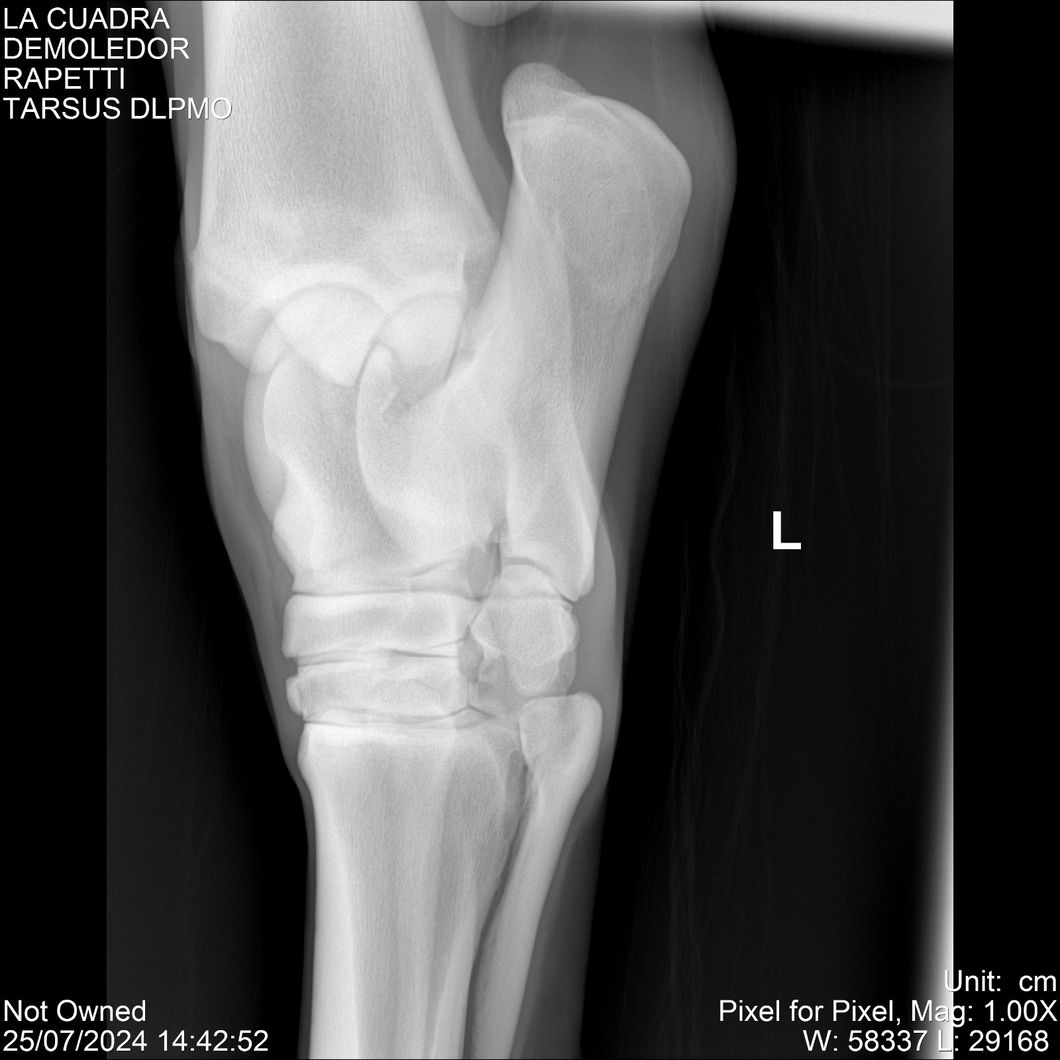

LOTE 14, DEMOLEDOR 🔥 🔥 🔥 Lote Anterior Volver al remate Lote Siguiente Ficha Contacto Montevideo - Ficha del Lote Identificador: #284454 Categoría: Yeguarizos Montevideo - 89 Visualizaciones ClicData Contacto Empresa: Abelenda N. R., Walter Hugo Nombre*: Teléfono* : E-mail* : Mensaje Enviar Registrese gratis Este contenido Exclusivo está disponible sólo para usuarios registrados Ingresar